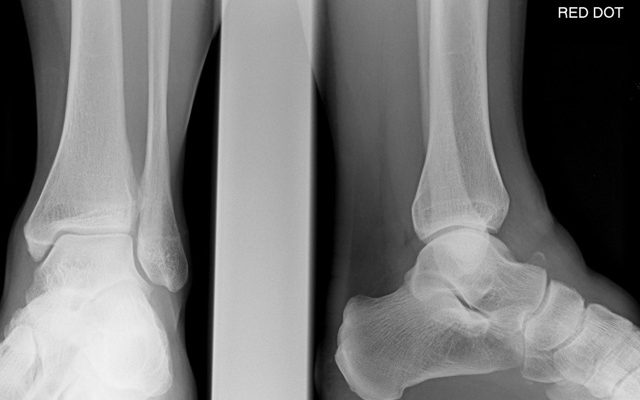

Помимо общего осмотра пациенту требуется комплексная диагностика. Для более тщательного изучения места перелома делают рентгеновские снимки. Вашему врачу потребуются боковые и передние снимки для подтверждения диагноза. Рентген делает шейку бедра полностью видимой.

Проекция Canale производится в зоне максимального эквинуса. Пронация — 15 градусов, снимок сделан под углом 75 градусов. Если изображение нечеткое или рентгенограмма не может быть сделана, выполняется компьютерная томография.

Для подтверждения диагноза делается рентген голеностопного сустава.